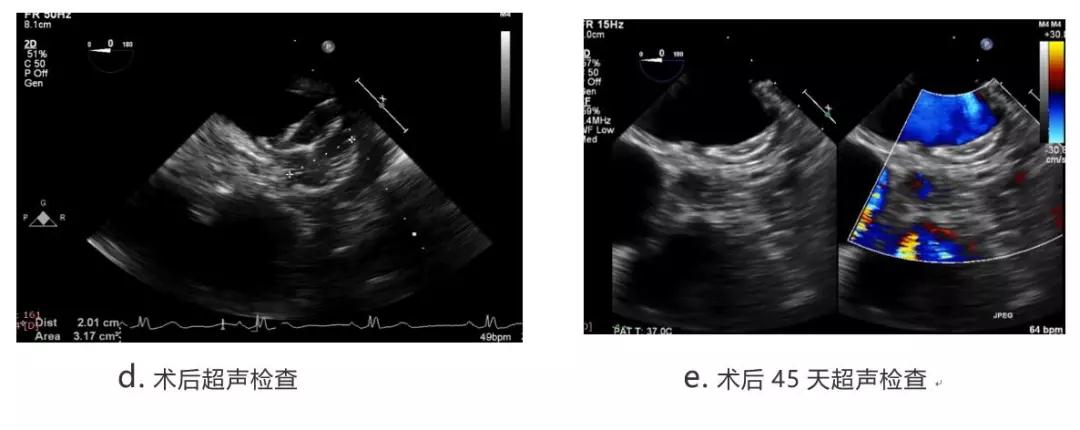

陶凌教授在报告中介绍到,目前西京医院已成功入组8例,器械均成功植入封堵左心耳,封堵器更换1例,手术顺利,术后患者均无不适,无手术并发症,各项指标正常,其中无残余分流6例,轻微残余分流(<2mm)2例。至今已有6例完成了45天随访,均无器械移位,无器械血栓,无并发症。

随后陶凌教授在会上分享两例患者术中造影及术后随访结果:第一位患者为65岁女性,左心耳为单腔结构,锚定区直径为26mm,第二位患者为58岁男性,左心耳为单腔结构,锚定区直径为21mm。二名患者均在全麻下经导管植入诺茂医疗研制的SeaLA®左心耳封堵器,封堵器规格分别为SL-LAA-3237和SL-LAA-2428。